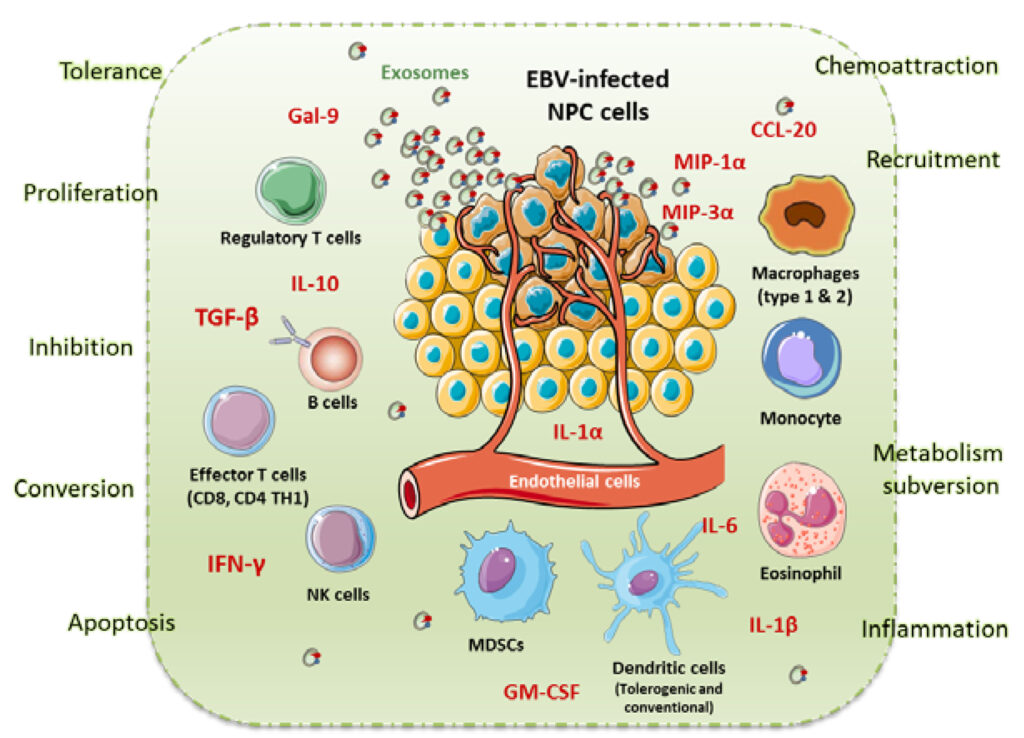

Mặc dù nguyên nhân chính xác gây ra ung thư vòm họng chưa được xác định nhưng một số yếu tố làm tăng nguy cơ mắc bệnh có thể kể đến như: nhiễm virus EBV, HPV, thường xuyên tiếp xúc chất độc hại, ăn nhiều thực phẩm muối lâu ngày, hút thuốc lá, yếu tố di truyền.